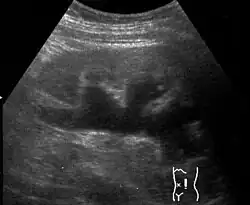

Massive hydronephrosis as marked by the arrow -

Renal ultrasonography of hydronephrosis[16]